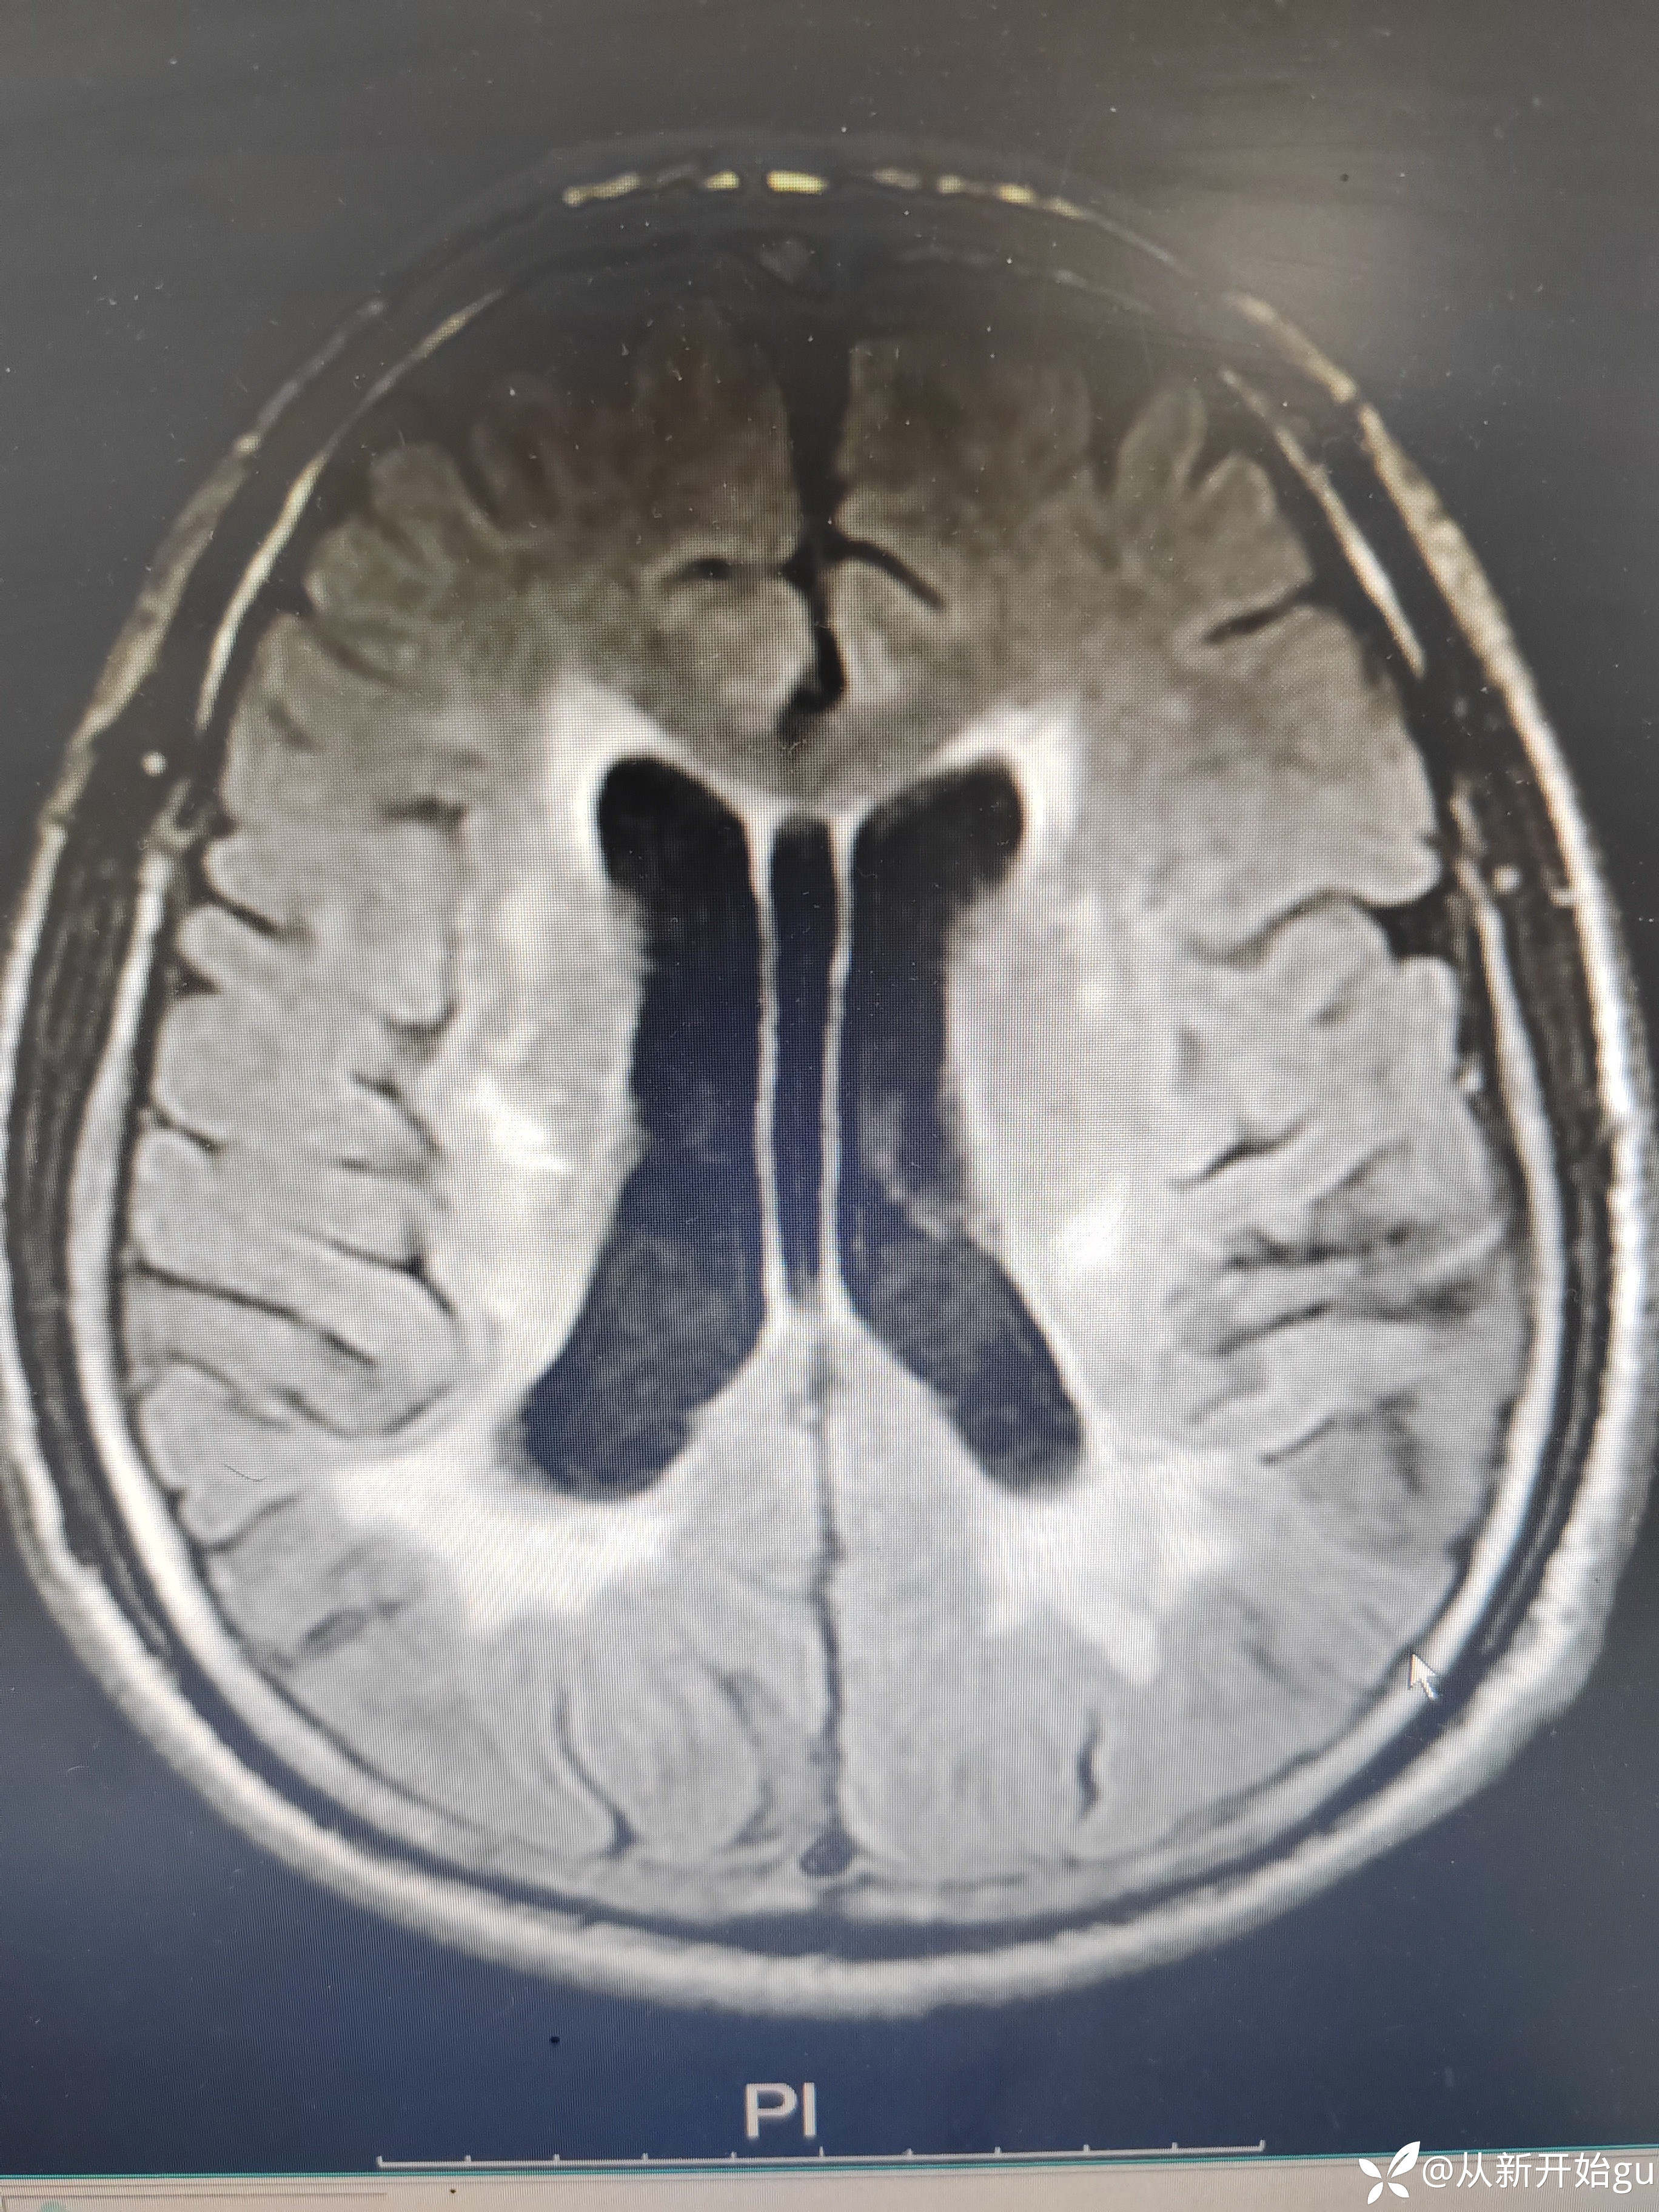

患者男性53岁,主因被发现左下肢活动障碍2.5小时来院,(患者下夜班,于上午9点休息,下午3点醒后出现症状)。既往脑梗死病史9个月,遗留言语不利及口角歪斜的症状。查体:右侧鼻唇沟稍浅,神舌右偏,左侧下肢肌力4级,左侧指鼻试验欠稳准,左侧巴氏征阳性。外院完善颅脑CT无出血改变。来院后完善核磁检查如图所示。